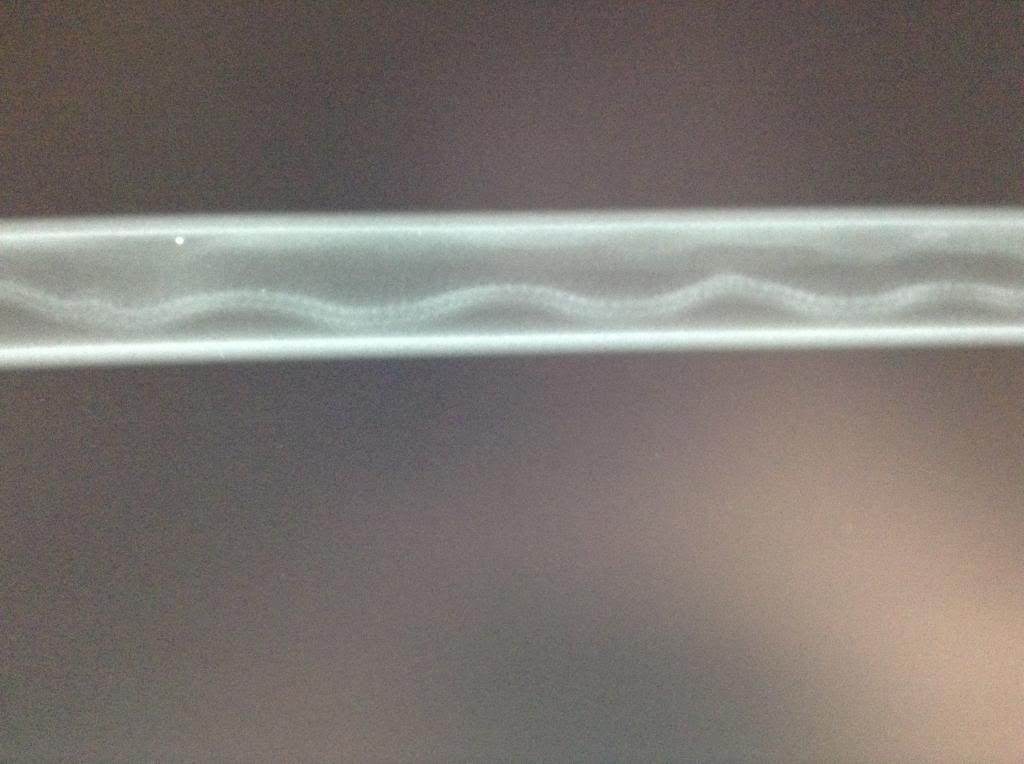

THEN he got stuffed (again, not literally) into a weird tube like device and carried around like a sword (not really) and was thus x-rayed a few different times.

Angry noodle in a tube!!! (he had scrunched himself up and wouldn't move lol)

Neck kink and one a little further down

Just past the neck, midway-ish down the body

A little further still

Even though he was scrunched up in the tube, you can clearly see where the kinks are :( poor little guy...my boss looked at 'em and thought he might (maybe) already be developing arthritis...wouldn't surprise me with kinks like that...

I believe the calcified areas that resemble arthritis are just calcified areas. I don't think I would sweat that too much, based on conversations I've had with my vet about kinked animals. The spine builds up buffers around the kinks, and they don't seem to be painful like arthritis.